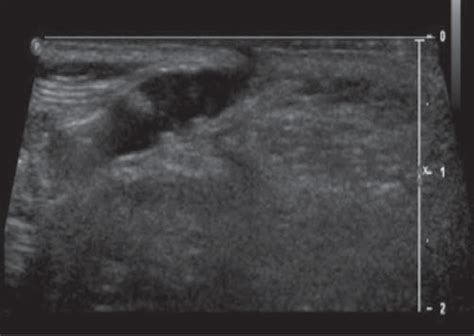

• Spinal Ultrasound: This is the gold-standard first test for infants younger than 4 to 6 months. It is safe, non-invasive, does not use radiation, and provides a clear picture of the spinal cord and surrounding structures.